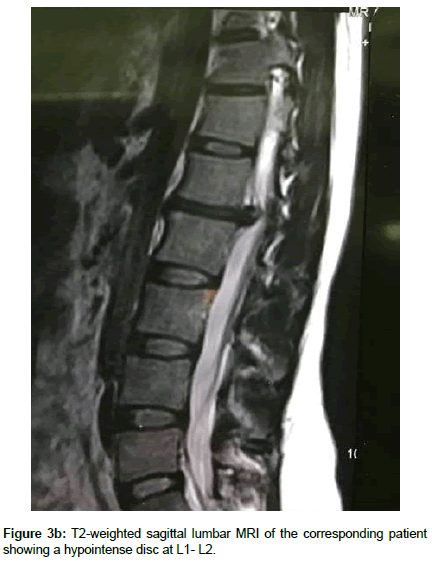

Operation time, the amount of intraoperative blood loss, and the post-operative time to return to routine work and daily life were documented. Clinical and radiological assessments were performed post-operatively and patients were followed up 1, 3 and 12 months after surgery. This follow up included a visiting at an outpatient clinic and telephone interview. As a radiological assessment, all cases had post-operative lumbar x-rays in early post-operative period and in 3, 6 and 12 months after surgery. An independent radiologist made radiographic evaluation based on dynamic lumbar x-rays, 3D CT scans and MRI. Clinical outcomes were collected and graded using the VAS for back and leg pain separately and functional outcomes were measured by ODI scores to quantify the impact of symptoms on patient’s everyday life [12,13]. Figures 1a-1h shows the clinical picture imaging studies and surgical results of three demonstrative patients (Figures 2a-2e and Figures 3a-3d).

A review of post-operative lumbar dynamic x-rays, CT scans and MRIs showed adequate decompression also bony union was seen in 33 of 37 patients (89.6%). Solid fusion was not achieved in 3 cases; still they were asymptomatic. There were no cases of pseudoarthrosis and symptomatic adjacent segment degeneration.